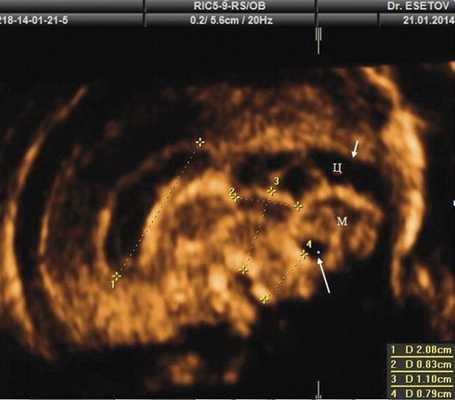

При изучении анатомии головного мозга плода в режиме 2D с применением стандартных аксиальных срезов во всех наших случаях мозжечок выглядел в виде овального образования однородной структуры с поперечным размером, менее уровня 5 процентиля для соответствующего срока беременности. При этом отсутствовала межполушарная выемка и область повышенной эхогенности по срединной линии мозжечка, характерная для отражения червя (рис. 1). На коронарном срезе также обращала внимание округлая однолобарная форма гипоэхогенного мозжечка (рис. 2). Использование трансвагинального подхода позволяло визуализировать дополнительно волокнистые структуры субарахноидального пространства (рис. 2).

Рис. 1. Аксиальные срезы головного мозга плода. Отражена картина однолобарного гипоплазированного мозжечка во всех наблюдениях.

а) Наблюдение 1.

Анализ сохраненных трехмерных изображений позволил получить более детальные характеристики структур мозга плодов с РЭС. На среднесагиттальном срезе в наблюдениях 1, 2 и 4 (в наблюдении 3 получить качественно этот срез не удалось) отмечено наличие атипичной полукруглой формы шатра (fastigium) 4-го желудочка, гипоэхогенная структура мозжечка с контрастирующим наружным контуром (рис. 3). При этом в первых трех наблюдениях отмечено полное отсутствие структур червя, тогда как в наблюдении 4 по контуру 4-го желудочка выявлены гиперэхогенные структуры, расцененные как передние отделы червя. Наличие передних отделов червя отражает и ряд послойных срезов в режиме TUI (рис. 4). У плода в наблюдении 4 также обращает на себя внимание относительное расширение надмозжечковой цистерны, с линейными структурами, при нормальной ориентации намета мозжечка (рис. 4).

а) Наблюдение 2, 3D. На эхограмме: 1 - боковой желудочек, 3v - 3-й желудочек, стрелки - контур мозжечка, пунктирная линия - шатер.

б) Наблюдение 4. На эхограмме: М - мозжечок.

На эхограмме: М - мозжечок, 4v - четвертый желудочек, короткие стрелки - фрагменты червя.

На эхограмме: М - мозжечок, Ц - цистерна, стрелка короткая - намет мозжечка, стрелка длинная - 4-й желудочек.